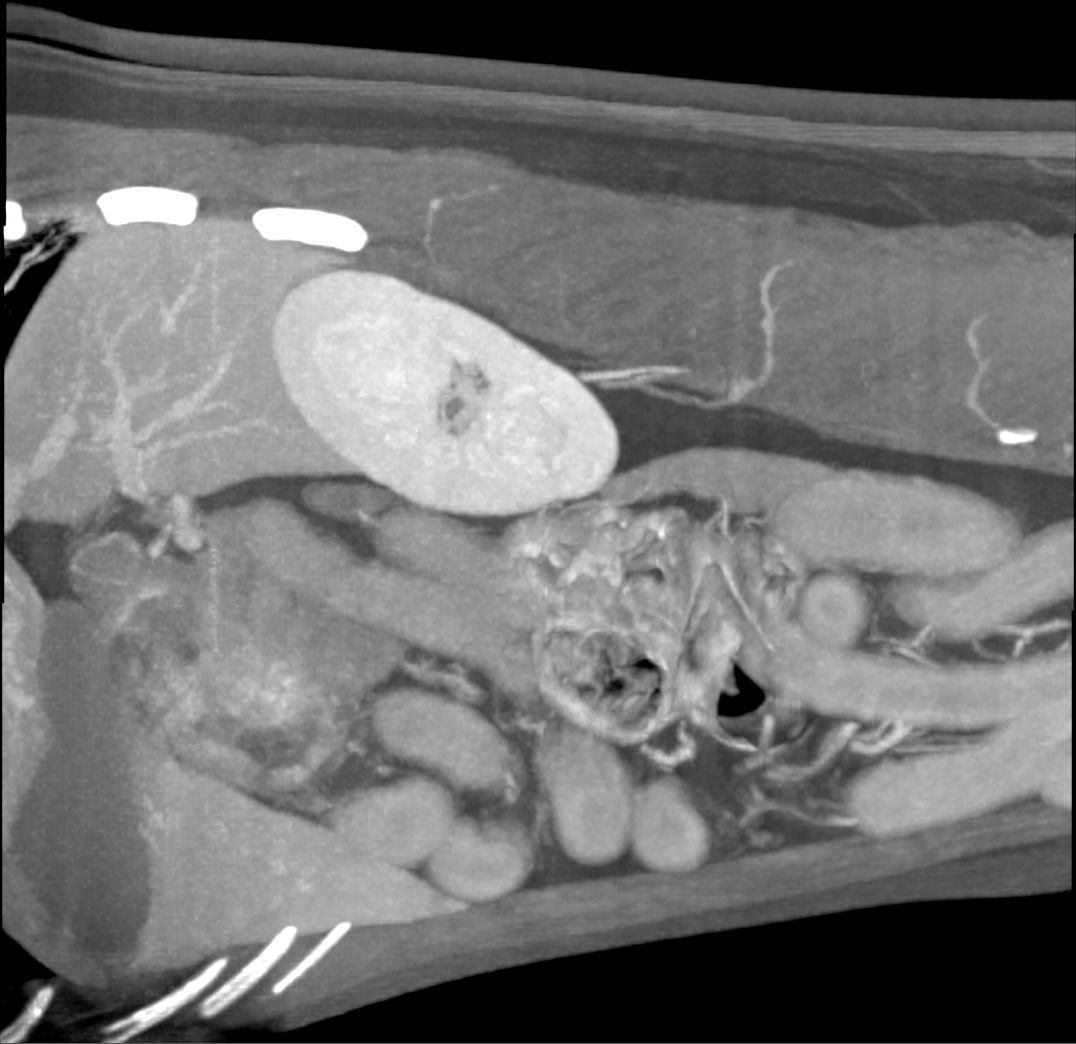

Liver Mass

Better Diagnostics=Better Care

The more information you can acquire for your pet when they are sick or hurt, the better recommendations your vet and our specialists can make.

It is a scary time when your pet needs advanced care.  Let us come to you to make sure you can make the best decisions for your pets care.